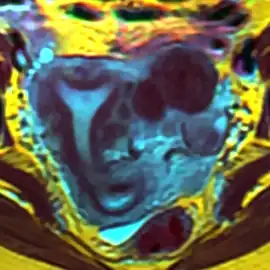

Se llama útero arcuato a una malformación uterina que se considera como una variedad del útero septado. En el útero septado la cavidad del útero está dividida de forma incompleta en dos partes por la existencia de un septo o tabique.

En el útero arcuato el septo no existe, pero se aprecia una convexidad en el fondo uterino que insinúa la formación de dos cavidades. Esta malformación es muy frecuente y en la mayor parte de los casos no ocasiona problemas de fertilidad ni otros trastornos y solamente se detecta al realizar pruebas específicas. Algunos autores consideran que el útero arcuato es una variante de la normalidad y no una anomalía, por otra parte su posible asociación con la pérdida precoz de embarazo u aborto espontáneo es controvertida y no está confirmada.[1] [2]